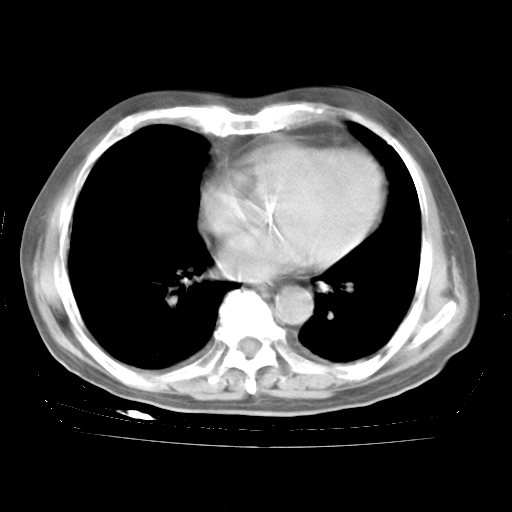

4月28日肺部CT——再次出现类似去年5月9日——透光度降低,“间质性”改变。

4月28日肺部CT——再次出现类似去年5月9日——磨玻璃样、间有“粟粒样”改变。

4月28日肺部CT